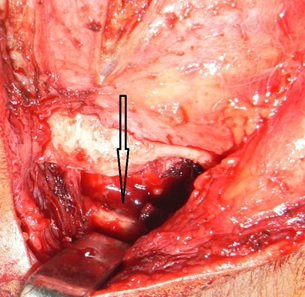

Surgical Procedure: All patients were operated under general anesthesia after written informed consent. Classical pre-auricular and Al-Kayat and Bramely’s modified pre-auricular incision were made as indicated to gain access to TMJ region of involved side [Table/Fig-3] [2,3]. Layer by layer dissection was carried out until superficial temporal fascia was reached. Superficial temporal fascia dissected out and retracted anteriorly to avoid injury to facial nerve. Periosteum over zygomatic arch was dissected and care was taken to avoid injury to superficial temporal artery and vein too. Ankylotic mass was exposed and belligerent excision of bony mass was carried out by chisel and bur with the gap of at least 10-15 mm between the floor of the glenoid fossa and the mandible [Table/Fig-4,5]. The glenoid fossa was recontured and shaped as necessary. Following excision of the bony mass the MMO of 30-35mm was achieved passively. In accordance with the protocol for TMJ ankylosis (1990, 2009) [4,5] contralateral coronoidectomy was performed in 4 cases through intra-oral approach when mouth opening was less than 35mm intra-operatively. Finger shaped composite temporal myofascial flap (includes temporalis muscle and fascia).

Classical pre-auricular Alkayat Bramely’s incision.